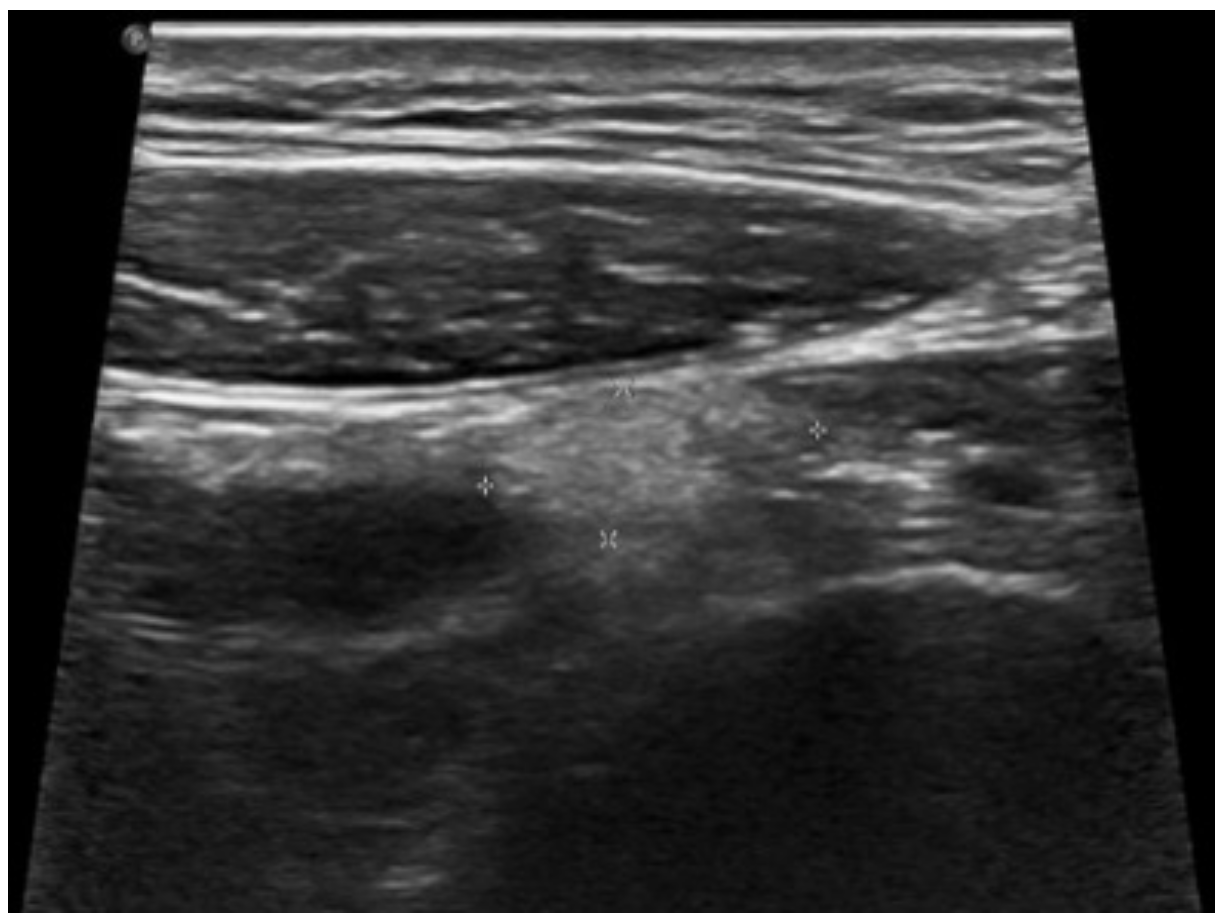

2. Case Report 1

3. Case Report 2